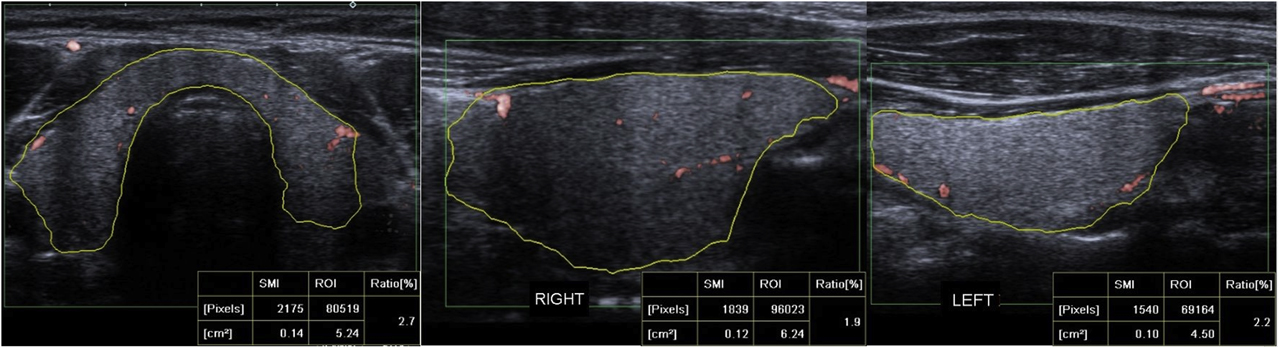

Vascular imaging of the thyroid gland used a pulse repetition frequency set to 150–180 Hz, with the same US device equipped with SMI function. VI measurements were performed on SMI images. Color SMI vascular investigation was performed on images enlarged to their maximum. According to plane, thyroid gland was investigated for 5 s using cSMI to measure VI, with the image then frozen. The VI calculation program was activated. Quantitative VI values were calculated following a manual drawing of the margins of the whole thyroid gland using free ROI. The 5 s image was investigated in reverse, and the highest VI values calculated for this period were noted. Greyscale pixels were eliminated and color pixels were automatically calculated. Quantitative VI values were obtained by calculating the ratio of color pixel numbers to total pixel count within the ROI. VI measurements were performed separately for right and left lobes in the longitudinal plane, then on the transverse plane including both thyroid lobes (Figure 2). The numerical values for VI for the right and left lobes in the longitudinal plane were added and divided by 2 to calculate the mean VI values for the whole thyroid gland in the longitudinal plane (longitudinal plane right mean VI value + longitudinal plane left mean VI value/2). Following this, mean VI in the longitudinal plane was added to the numerical VI value obtained for the whole thyroid gland in the transverse plane. The total value was divided by 2, and the mean VI value for the whole thyroid gland was calculated (thyroid gland mean VI = [mean VI for thyroid gland in longitudinal plane + mean VI for thyroid gland in transverse plane]/2).

Quantitative SMI VI values were measured by manually drawing the contours of the thyroid gland structure on the cSMI mode, in the longest transverse plane, right lobe, and left lobe longitudinal plane. The quantitative VI values measured 2.7% in transverse plane, 1.9% in right lobe longitudinal plane and 2.2% in left lobe longitudinal plane.